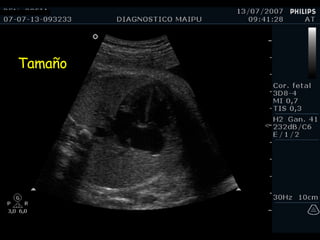

Tamaño